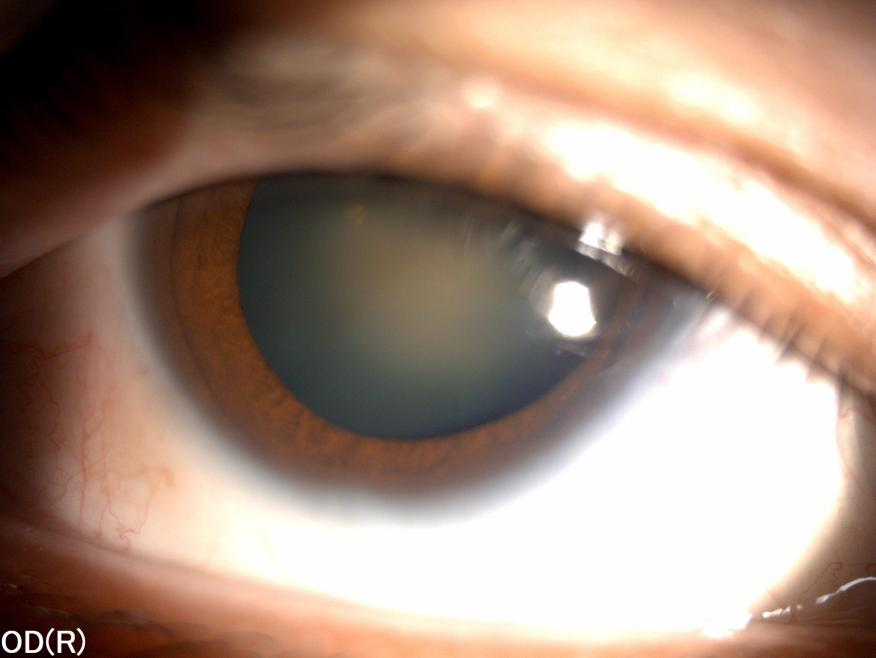

近日,39 岁的张先生视力骤降,而且在照镜子时,发现眼珠竟然没有之前黑了,看上去还「泛白光」。本以为只是近视度数加深,可没想到前往武汉普瑞眼科医院检查后,发现竟是重度白内障,近视度数更高达 2500 度。

最终,他前往武汉普瑞眼科医院求助。经过 20 余项的专业检查,最终医院确定张先生 2500 度,合并严重白内障、弱视、干眼等多重问题,单纯进行近视手术已无法解决他的需求问题。在多学科联合会诊(MDT)下,张先生被转往屈光性白内障专科进行治疗。

最终,根据张先生的检查结果及沟通本人的意愿需求,医生为他制定了「飞秒激光辅助白内障手术+张力环植入术+三焦点人工晶体植入术」,一次解决了他的高度近视及白内障双重问题。据白内障专科主任阮丽娟介绍,张先生的高度近视已经导致他晶状体悬韧带松弛,若不治疗,一方面高度近视极易引发视网膜裂孔、视网膜脱离等严重问题;另一方面,白内障病情将持续加重,还会引起青光眼、葡萄膜炎等多种不可逆的并发症风险,因此结合他本人对远中近视力的需求等多重因素,才定制了该套解决方案。